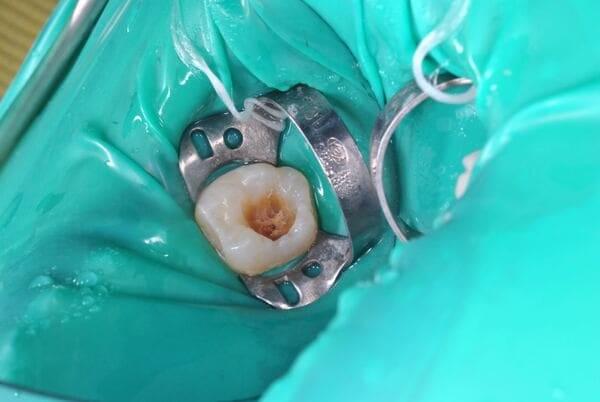

Поява перших постійних зубів, а це шості зуби, відбуваються, коли дитина ще не може, як слід провести їх гігієну та попіклуватись про їх здоров’я. Тому, на жаль вони і вражаються карієсом досить швидко. Пацієнт ще маленький – 6 років, а лікування потребує дорослого: зі знеболенням та ізоляцією. Саме таке і було проведене в даному випадку: зуб очищений від інфікованих тканин, відновлений фотополімерним матеріалом і готовий довго служити юному господарю.